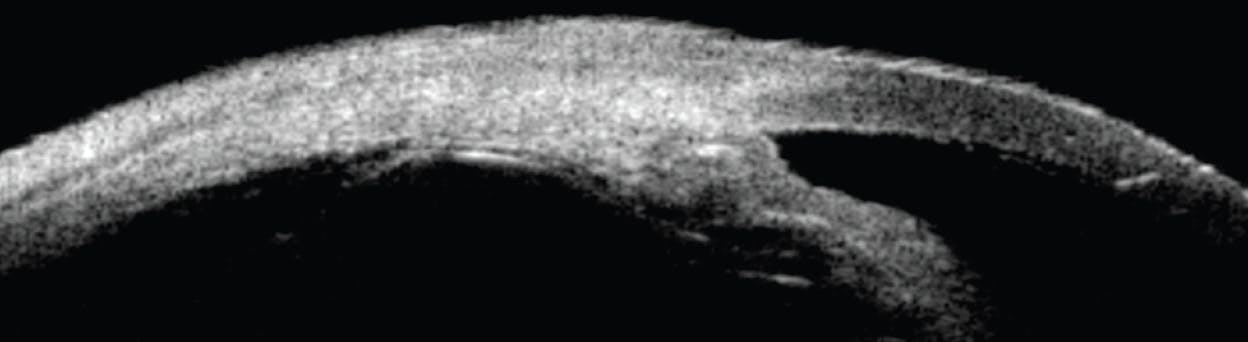

B-scan ultrasound biomicroscopy (UBM) is highly useful in revealing vitreous opacities and can be compared with the fellow eye and interval follow-up for patients with vitritis. B-scan can also highlight associated retinal pathology when there is no view. Fluid in the sub-tenon space (posterior scleritis T-sign), granulomas, and choroidal thickening can be identified on B-scan UBM. Extraocular lesions of MALT lymphoma hugging the globe can also best be seen on B-scan UBM. This imaging modality allows for the evaluation of the ciliary processes (Figure 7), and it can help clinicians investigate for rare causes of ocular inflammation, such as uveitis-glaucoma-hyphema syndrome, ciliary body malignancy, and even hidden intraocular foreign bodies.

Figure 7. UBM showing atrophy of the ciliary processes in a patient with hypotony receiving CAR-NK infusions.